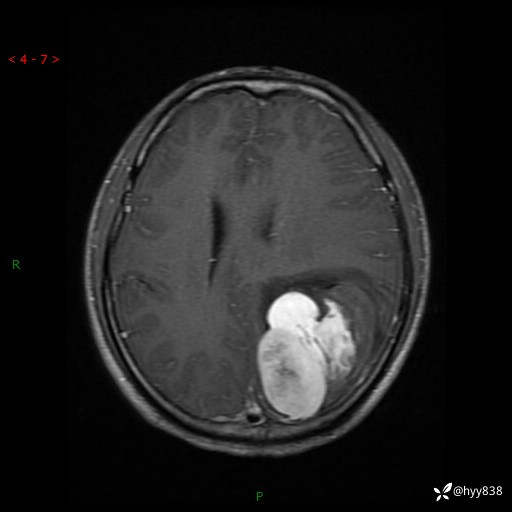

性别:男

年龄:21岁

简要病史:头痛伴呕吐半年,渐进性加重1月

颅脑MRI平扫+增强